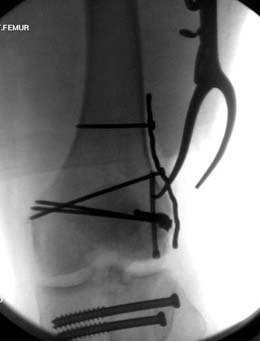

При изолированных переломах можно лечить миниинвазивно каннюлированными винтами, но в большинстве Hoffa компонент сопровождается другими типами перелома дистального бедра. Выбор доступа зависит от расположения фрагментов и большинстве латеральный субвастус доступ подойдет для фиксации перелома.

В данном случае предпочтителен парапателлярный доступ, где необходимо создать лучший обзор к мыщелку. После остеотомии и репозиции фиксацию надо проделать поперечными винтами и дополнительно задней antiglade plate - сделанной из 1/3 tubular plate.

Здесь представлены различные варианты фиксации перелома, а также снимки комбинации перелома с повреждением хряща (12-19). Пластика хряща OsseoFit и установка custom made plate.